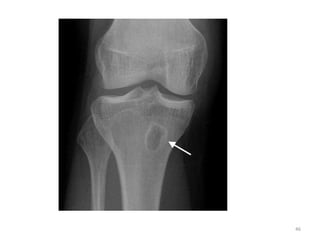

• Common in children

• Metaphysis around the knee joint is

commonly involved in children.

• Localized osteoporosis and bone resorption caused by

infection in the medullary space with hyperemia, edema

or abscess formation, and trabecular destruction occur.

• Later, there is increased lysis and cortical lucency as

infection spreads into the haversian and Volkmann's

canals of the cortex.

• Next are periostitis and involucrum formation, which are

caused by subperiosteal abscess formation with lifting of

the periosteum and bone formation .

Bone Changes:

• Bony changes –

- 10-14 days required

– Local osteopenia (at the site of infection,

usually metaphysis) is the earliest bony

change.

– Periosteal reaction follows

– An involucrum is usually visualized after 3

weeks

– Sequestrum is seen as dense, irregular bone

surrounded by lucency (representing

granulation tissue).

– Cloacae (fistula tract) are seen as lucent

areas which are created by external

migration of dead pieces of bone with

breakdown of skin and subcutaneous tissue.